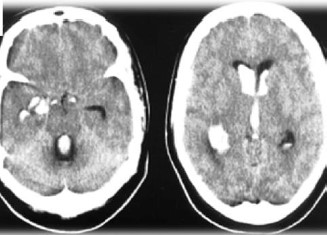

Paciente feminina, 60 anos, levada ao PS por cefaleia súbita, seguida de sonolência, confusão mental e hemiplegia esquerda. A Tomografia foi realizada e apresentou os seguintes achados:

Enunciado 3161924-1

Sobre o caso descrito, assinale a alternativa CORRETA: